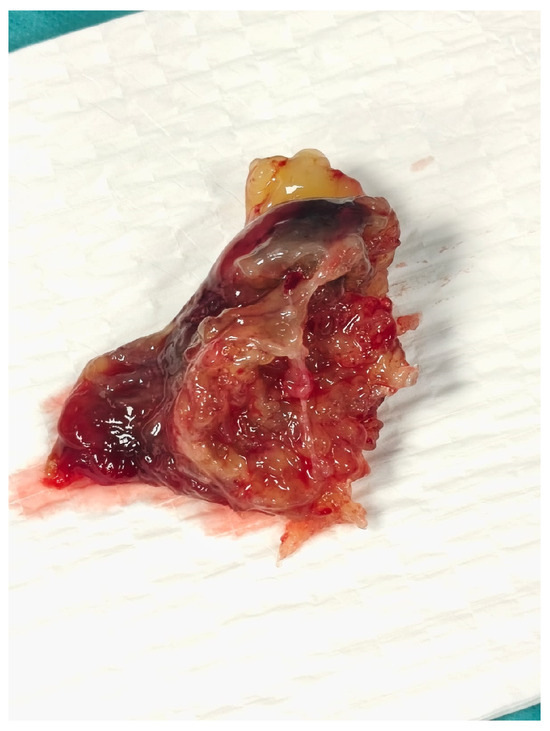

Given the critical obstructive physiology and life-threatening presentation, the patient underwent urgent surgical excision of the mass via median sternotomy under cardiopulmonary bypass (Figure 2). Upon opening the left atrium, a gelatinous mass was identified, attached to the interatrial septum via a narrow pedicle. The tumor measured approximately 3.7 × 4.5 cm and exhibited a lobulated, irregular surface (Figure 3). These findings accounted for the severe dynamic obstruction of the mitral orifice observed preoperatively and underscore the capacity of left atrial myxomas to precipitate acute, life-threatening obstructive disease. Intraoperatively, the mass was friable and gelatinous, with focal areas of increased density suggestive of fibrous components, consistent with a mixed morphological pattern. Its marked mobility and fragile texture raised concern for embolic potential, characteristic of the macroscopic features of cardiac myxomas. The tumor was completely excised at its point of attachment, without requiring interatrial septal resection or reconstruction.

Figure 3. Gross specimen of the excised left atrial myxoma, measuring approximately 3.7 × 4.5 cm, with a lobulated and irregular surface.